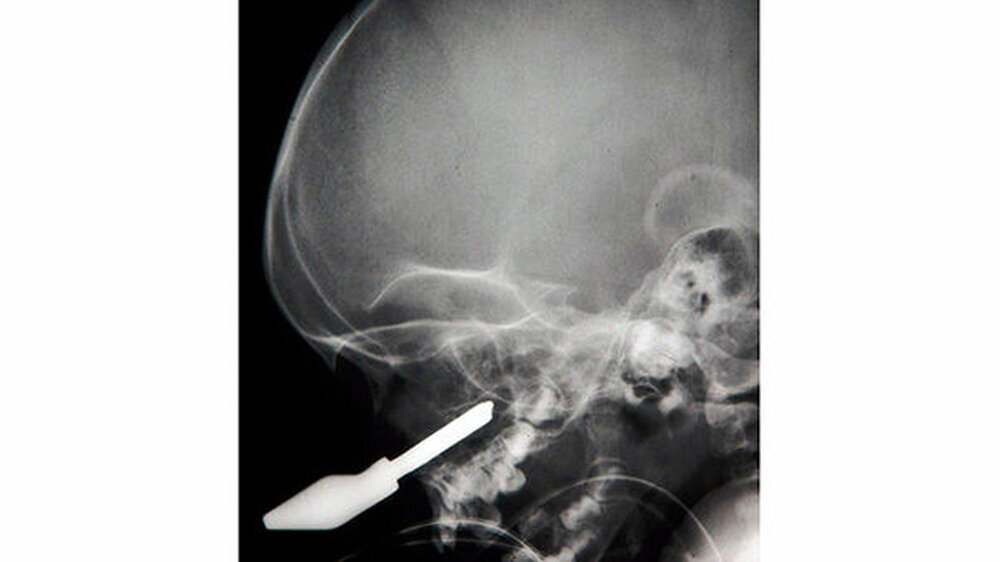

Fremdkörper im Gesicht

Vom Bohrer im Kopf bis zum Schlüssel in der Kieferhöhle: Die MKG-Chirurgen der Charité haben ausgewählte Patientenfälle mit Fremdkörpern im Gesicht zusammengestellt. In unserer Fotostrecke finden Sie die eindrucksvollen Aufnahmen.